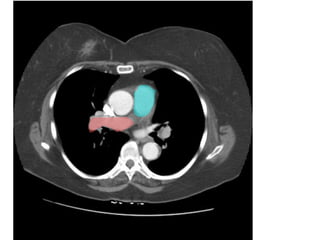

Figure 9. PE ở bn nữ 42 tuổi, đau ngực và khó thở nhiều.

- Hình ảnh thất phải dãn lớn hơn thất trái.